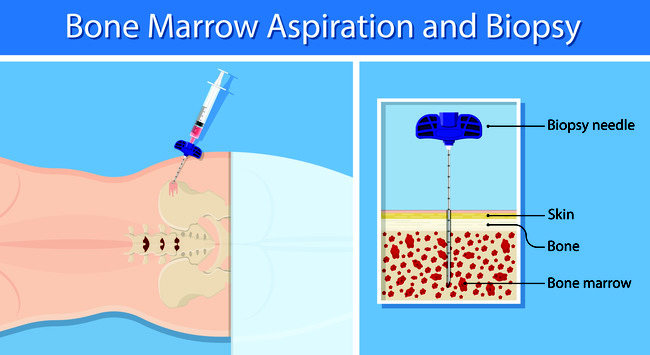

Aspirasi Sumsum Tulang Ini Yang Harus Anda Ketahui Alodokter

Aspirasi Sumsum Tulang Ini Yang Harus Anda Ketahui Alodokter

Tes Sumsum Tulang Pemeriksaan Yang Wajib Dijalani Pasien Kanker Darah Honestdocs

Tes Sumsum Tulang Pemeriksaan Yang Wajib Dijalani Pasien Kanker Darah Honestdocs

Aspirasi Sumsum Tulang Ini Yang Harus Anda Ketahui Alodokter

Aspirasi Sumsum Tulang Ini Yang Harus Anda Ketahui Alodokter

Tes Sumsum Tulang Pemeriksaan Yang Wajib Dijalani Pasien Kanker Darah Honestdocs

Tes Sumsum Tulang Pemeriksaan Yang Wajib Dijalani Pasien Kanker Darah Honestdocs